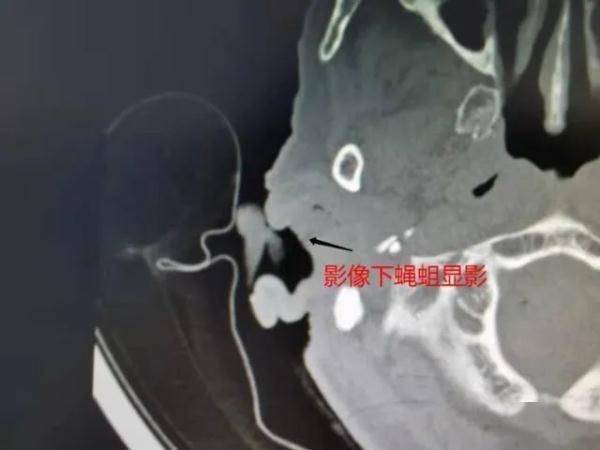

【蛆虫|吓一跳!大理80岁老奶奶耳朵里取出20条活蛆】值班医生用手电筒照射王奶奶的右耳肉眼初步观察 , “咦 , 耳朵里还填满了白色纱条啊 , 那得抽了纱条才看得清啊 。 ”再仔细检查后发现 , 这些“白色纱条”居然还会自己“蠕动” 。 原来 , 这些像纱条一样的东西竟然是活体蝇蛆 , 而且数量还不少!

医生让王奶奶完成了其他检查后 , 决定先为其取出堵塞在耳道里的活体蝇蛆 , 再做系统的病因分析并制定出行之有效的诊疗方案 , 从根源上解决疾病 。 于是医生立刻在视屏耳内镜下进行专业处理 , 共取出约20余条活体蝇蛆!

耳鼻喉科陈银忠主任医师在详细查阅分析王奶奶的病历后 , 找到了王奶奶右耳中有蝇蛆的原因——王奶奶右耳外耳道及鼓室存在病灶 , 引发其右耳反复流脓 , 招引了苍蝇叮咬产卵 , 最终导致活体蝇蛆寄生在耳道中(临床中的蝇蛆病) 。